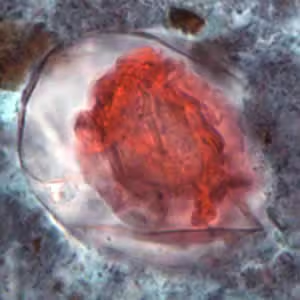

Hymenolepis proglottids.